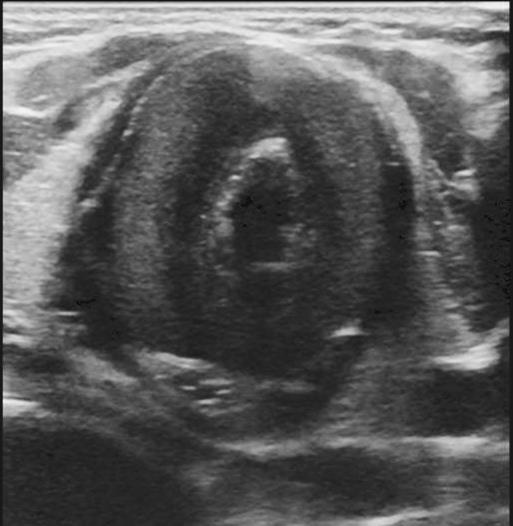

Pediatric COVID-19: MIS-C (Multisystem inflammatory syndrome –Covid)

• Serious condition where different body parts can be inflamed

• Characterized by severe, febrile inflammatory illness

• Elevated inflammatory markers

• "Cytokine storm

• 2 - 4 weeks after infection or exposure

• 80 - 100% + SARS-CoV-2 antibodies

• School-age children

Pediatric COVID-19: MIS-C

Thoracic abnormalities

Abdominal abnormalities

Solid viscera abnormalities

Hepatomegaly

Echogenic kidneys

Splenomegaly

Hollow viscera abnormalities

Gallbladder wall thickening

Bowel wall thickening

Bowel dilation

Gastric distention

Urinary bladder thickening

Peritoneal abnormalities

Small ascites

Mesenteric abnormalities

Mesenteric lymphadenopathy

• Gastrointestinal (GI) symptoms (abdominal pain, diarrhoea and vomiting) are prevalent in MIS-C

• Abdominal pain in 62%

• Up to 90% any GI symptom

• Anumber of studies have described abdominal imaging findings including ascites, bowel wall thickening and mesenteric lymphadenopathy